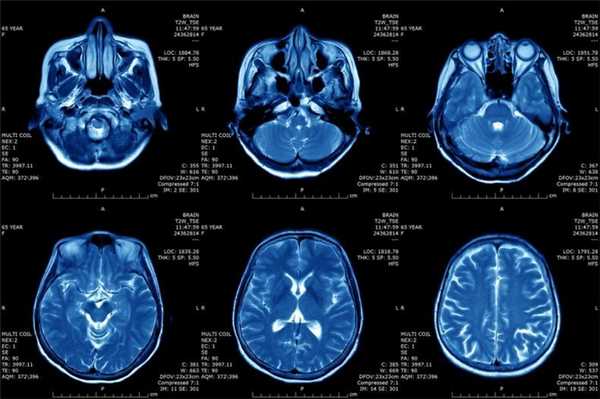

Что покажут снимки МРТ шеи у ребенка с лимфангиомой

- Заполненное жидкостью образование хорошо визуализируется на Т2-взвешенных изображениях

- Интенсивность сигнала на Т1-взвешенных изображениях зависит от содержания белка и наличия кровоизлияний

- Возможен уровень жидкости в пределах кисты (кровоизлияние)

- Отсутствие определяемого кровотока

- Умеренное контрастное усиление перегородок

- Имеется объемный эффект.

МРТ в режиме подавления сигнала от жидкости. Лимфангиома (стрелки) имеет гиперинтенсивный сигнал. Окологлоточный компонент опухоли смещает и сдавливает просвет глотки.